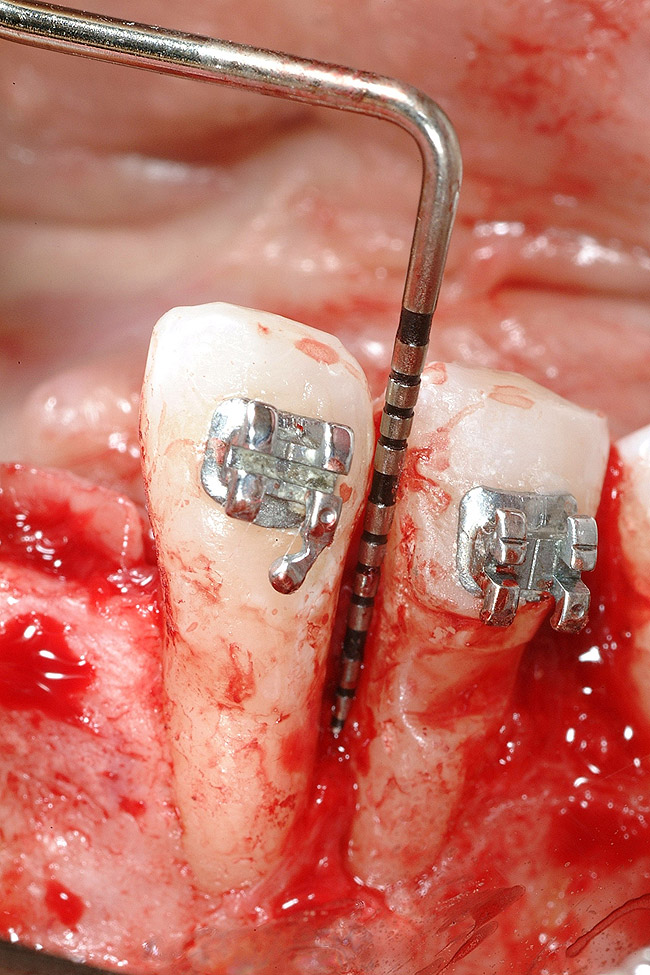

Figure 4  Vertical ridge defect in site No. 22.

Figure 4

Figure 5  Horizontal ridge defect in site No. 22.

Figure 5

Following the first goal of orthodontia—moving tooth No. 22 to a proper functional and anatomical position—a periodontal reevaluation was performed, demonstrating an improvement in short- and long-term tooth prognosis. At this time, the decision was made to abort continual extrusion of teeth Nos. 21 and 22, although some attachment level discrepancy remained between Nos. 21 and 22 (Figure 14). Implant diagnostics ensued and included mounted study models and a diagnostic wax-up. A scanning appliance was created to demonstrate the desired prosthetic outcome requirements, and the patient was referred for computed tomography (CT) scans. CT scan assessment demonstrated successful orthodontically directed GBR to allow implant placement (Figure 15 through Figure 16). Only minor GBR therapy would be needed and could be accomplished simultaneously with implant installation. Guided implant placement occurred, using an open flap approach (Figure 17). During surgery, root dehiscences were noted on teeth Nos. 21, 22, 24, and 25, as well as the anticipated dehiscence following implant placement at No. 23 (Figure 18). A positioning reference (index) was secured after implant placement to facilitate a provisional prosthesis at stage II surgery. Cortical perforations then were placed adjacent to the implant to encourage angiogenesis (Figure 18), and mineralized freeze-dried bone allograft enhanced with platelet-derived growth factor was placed over the dehiscences for purposes of guided tissue regeneration and GBR (Figure 19). A highly resorbable collagen membrane was placed to stabilize the allograft. The flap was coronally repositioned, and primary-intention wound healing was achieved (Figure 20 and Figure 21). Following 4 months of stage I surgery, implant uncovery and immediate provisionalization were performed in conjunction with connective tissue grafting. Final orthodontic tooth movement then ensued, using the implant as anchorage to optimize end-tooth movements, interroot separation, and the cuspid-protected occlusal scheme. A final impression then was secured, and a zirconia abutment (Figure 22) with an all-ceramic restoration was fabricated for the prosthetic phase completion of No. 23 (Figure 23 through Figure 25).